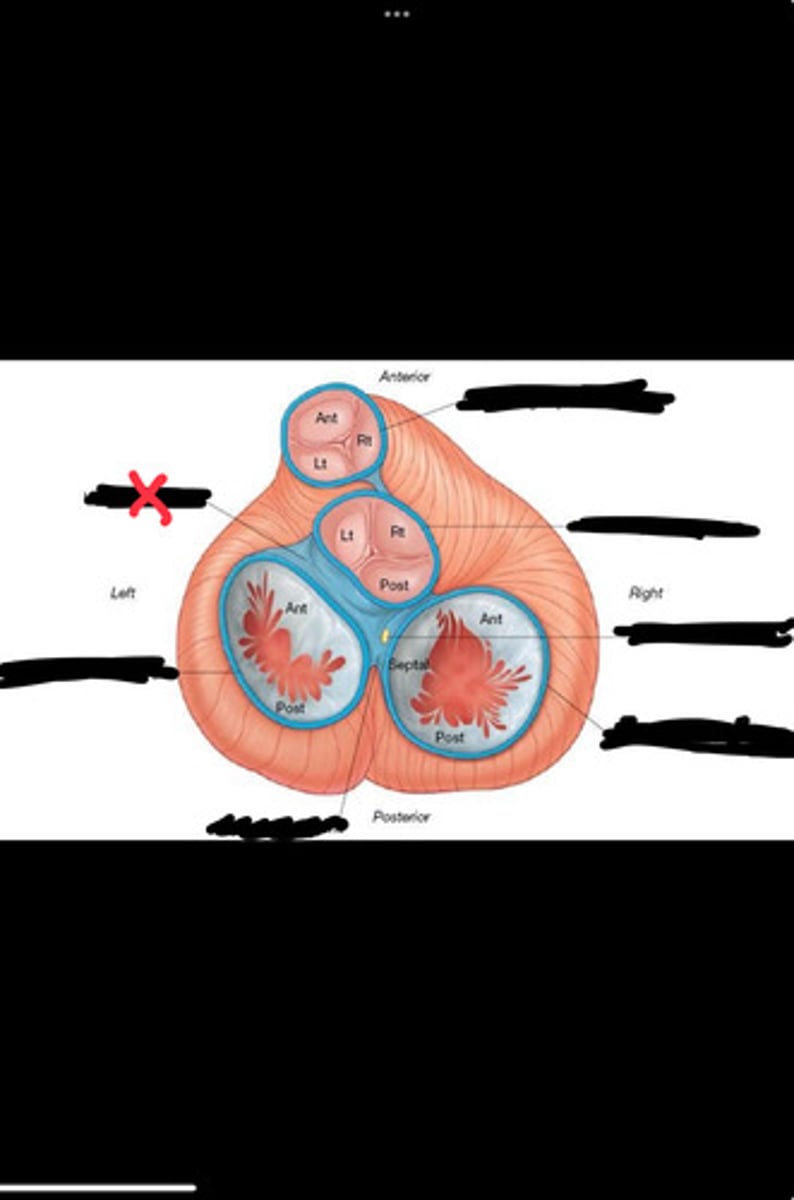

Right fibrous trigone

Left fibrous trigone

Fibrous ring of pulmonary valve

Fibrous ring of aortic valve

Atrioventricular bundle

Right atrioventricular ring

Left atrioventricular ring